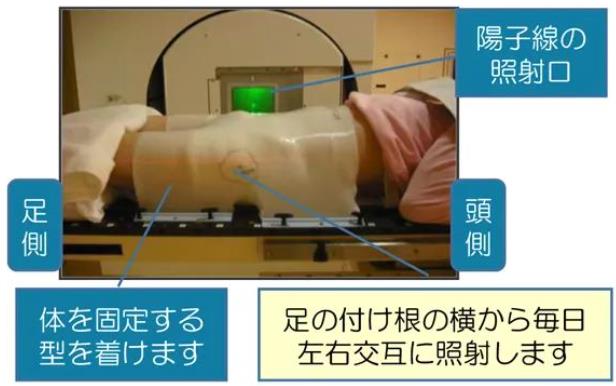

2.在治療床上需要保持一個姿勢約60分鐘。

每個人的前列腺大小以及與距離直腸和膀胱的距離都不同,就像身高和體重不同一樣。因此,在使用質子治療前要針對每個患者設定范圍和深度。另外,在照射前,對盆內部進行X射線拍攝,以1mm為單位調整前列腺的位置,進行準確的治療。

治療次數和持續時間取決于疾病的狀況(癌癥類型和大小等)。每周周一~周五門診治療5天,持續約5周。一次治療大約需要15~30分鐘。照射本身只需要幾分鐘。